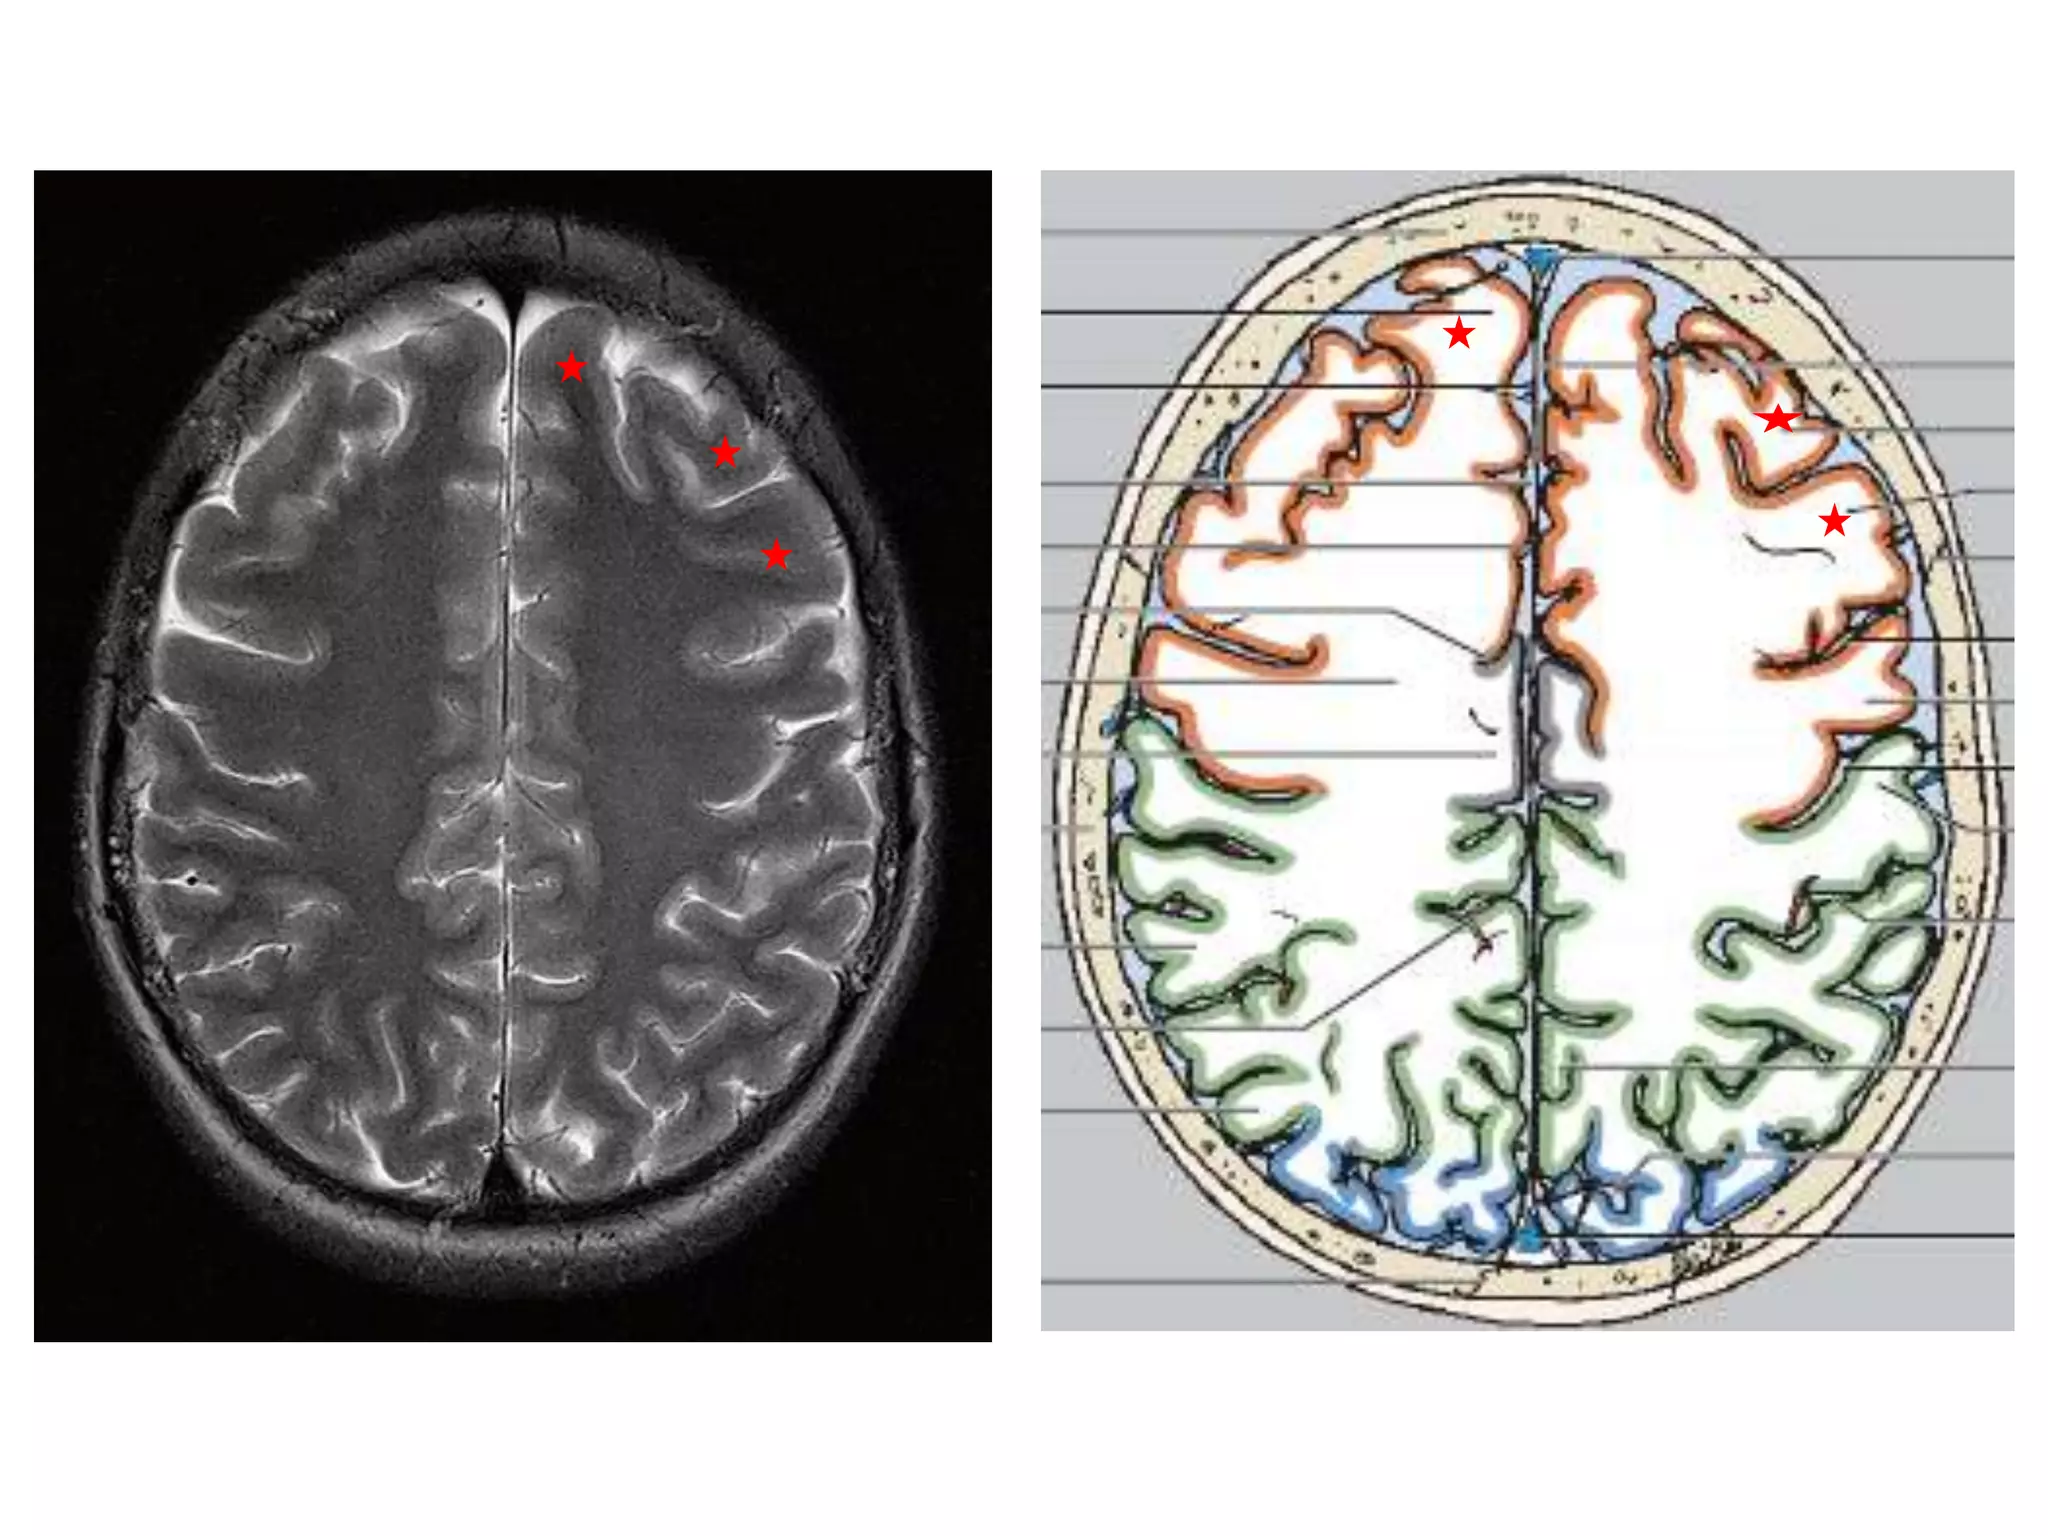

CENTRAL SULCUS (Rolandic fissure)

AXIAL :

1. Tracing from superior frontal sulcus.

2. Similarly interparietal sulcus intersects post

central sulcus

3. Precentral : Post central gyral grey matter

thickness = 1.5 :1

4. Peri rolandic cortex more hypointense on FLAIR.

CEREBRAL HEMISPHERES • 4lobes are present in each hemisphere. They are demarcated by fissures. • Each lobe is again divided into gyri by sulci . They are named accordingly. • Anatomy of cerebral hemispheres and mid brain – T1 W MRI. • Internal grey - white matter areas – T2 W MRI. • In Cerebral hemispheres , white matter above the level of lateral ventricles is called centrum semiovale